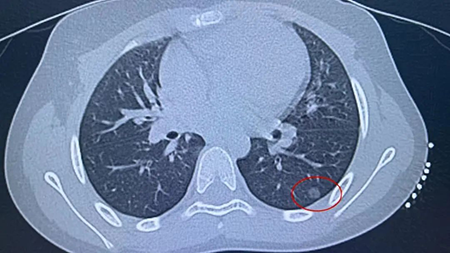

【精选文章】4岁孩子因咳嗽查出肺结节!呼吸道疾病肆虐,家长需警惕!